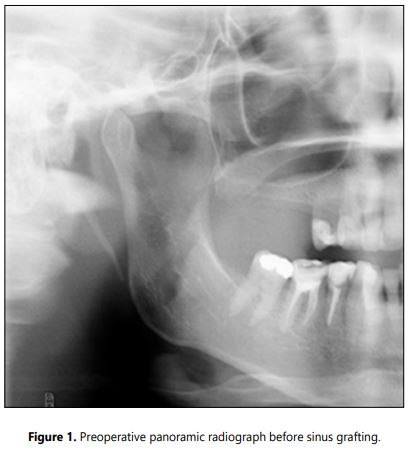

Radiographic examination: The CBCT or panoramic X-rays were performed pre-surgically and before the implant placement to evaluate the bone formation (Figures 1 and 1a). Intraoral X-rays were accomplished six months after implant placement and then annually to asses marginal bone loss. The success rate was determined using the Albrektsson et al. criteria [18].

Radiographic examination: At the time of the implant placement the mean of the bone gain was 11.91 mm ± 2.80 mm. The new bone volume in all the cases allows the subsequent implant installation. At the 5-year follow up examination the marginal bone reduction showed minor changes.